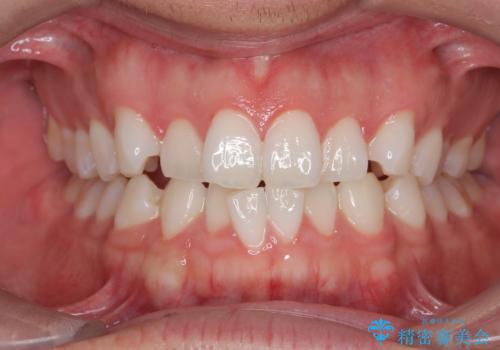

[マウスピース矯正] がたがたの歯並びをきれいにしたい

![[マウスピース矯正] がたがたの歯並びをきれいにしたいの症例 治療前](https://seimitsushinbi.jp/wp/wp-content/uploads/2025/06/0d238550c8a0fddc4de7b2c337c6c786-500x350.jpg?v=1750323380)

![[マウスピース矯正] がたがたの歯並びをきれいにしたいの症例 治療後](https://seimitsushinbi.jp/wp/wp-content/uploads/2025/06/IMG_0002-2-500x350.jpg?v=1750323305)